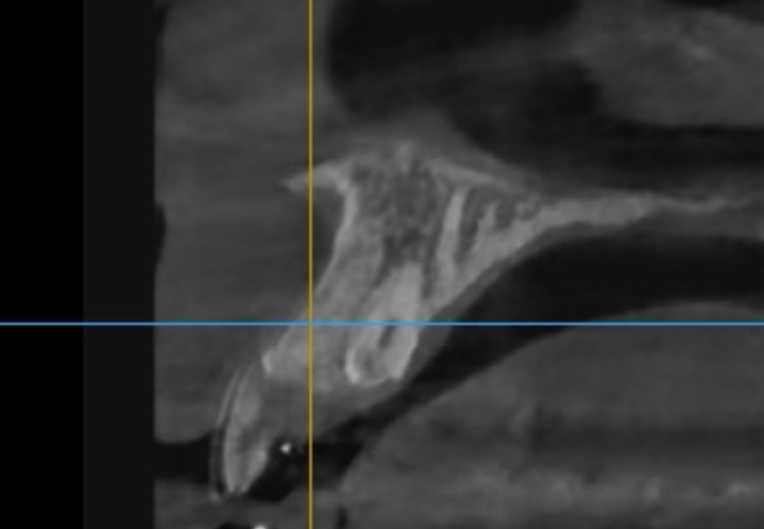

과잉치 발치후 치조골 재생됫는지

과잉치 발치후 8개월이 지났는데요

저정도 재생된 치조골이면 사용하는데 이상이 없은건가요?

또한 정상적인 앞니 치조골에 비해 적은 편인가요?

저정도 상태라면 치조골이 많이 재생이 된거 같습니다. 시간이 지나면 치조골이 더 생길거 같으니 너무 걱정하지 않으셔도 될것같습니다.

과잉치아를 발치하고 나면 대부분 잇뼈가 차오르게 됩니다. 시티상으로 봤을 경우에도 잇몸은 잘 차오르고 있는 것으로 보이며 크게 문제가 있어 보이지는 않습니다.

과잉치와 함께 형성되어 있던 물혹이 있었던 것 같고 그 부위는 아직 뼈가 채워지지는 않았습니다 술후 불편감이 계속 지속되었다면 치과를 가보시는게 좋겠습니다